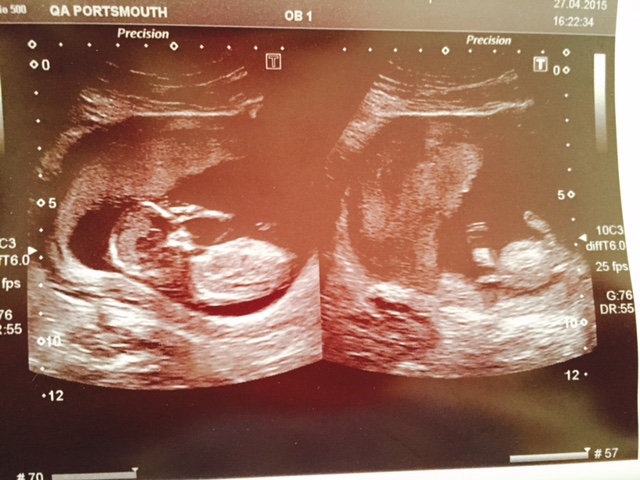

Here are my scan pictures from my scan yesterday, I am 13 weeks and 2 days when the pictures were taken :)

Boy or girl?!

Alot of lines going on there, I think I would be a tiny lean girl too but the detail is mostly missing so a boy nub could easily be just off of shot somewhere 51/49 pink :)

Slight girl lean. Agree with 51/49 split